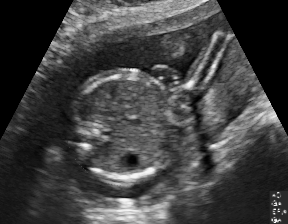

| 4CH | Abdominal | Femur | Lips | LVOT | |

| SF | |||||

| SC | ![]() |

![]() |

We demonstrate the practical applicability of our method on a challenging medical application, the classification of standardized fetal ultrasound (US) views during prenatal screening. In many countries, US imaging is clinical routine for prenatal health care. The classification of standardized views is important for a consistent, cross-institutional identification of possible abnormalities [47]. Early detection of pathological development can inform following treatment and delivery options [55, 25]. DNNs have shown promising performance to support this task [2]. However, ultrasound images are often hard to interpreted [40]. Anatomical structures have inconsistent appearance [2] and contain different orientations and shapes of anatomical landmarks [1]. Labeled training data is often insufficient as annotating medical images requires significant expertise and is prohibitively expensive in both time and labor. Manifestation of acoustic shadows [17, 44] as shown in Fig. 2(a) as well as different imaging devices as shown in Fig. 2(b) can lead to a domain shift problem for vanilla DNN classifiers. Exploring domain adaptation in fetal US enables DNN classifiers to be effectively utilized on a wider range, which supports identification of abnormalities from varying data sources. This can benefit prenatal healthcare.

We evaluate the proposed method on two fetal US standard plane classification tasks, where the domain shifts are respectively caused by shadow artifacts (Fig. 2(a)) and different image acquisition devices (Fig. 2(b)). For both tasks, images from source and target domains are unpaired and collected independently. We show the key results in the main paper and detailed implementation, network architectures as well as more results in the supplemental Appendix.

The fetal US dataset consists of 2D fetal US images sampled from 2694 2D US examinations with gestational ages between weeks (iFIND Project 555http://www.ifindproject.com/ ). Eight different US systems of identical make and model (GE Voluson E8) were used for the acquisitions to eliminate as many unknown image acquisition parameters as possible. Six different anatomical standard plane locations have been selected by an experienced sonographer, including Four Chamber View (4CH), Abdominal, Femur, Lips, Left Ventricular Outflow Tract (LVOT) and Right Ventricular Outflow Tract (RVOT). The images have additionally been classified by an expert observer as shadow-containing or shadow-free. In this experiment, the source domain contains shadow-free images (see Fig. 2 (b) SF) while the target domain has shadow-containing images from less favorable imaging conditions (see Fig. 2 (b) SC). Training data consists of all six standard planes from the source domain as well as Abdominal, LVOT and RVOT from the target domain. We aim to separate anatomical features (categorical features) and shadow artifacts features (domain features) to obtain generalized anatomical features for achieving high performance of standard plane classification on (4CH, Femur and Lips from target domain). Here, contains 4CH, Abdominal, Femur, Lips, LVOT and RVOT from the source domain and contains Abdominal, LVOT and RVOT from the target domain. Hyper-parameters to in Eq. 11 are for the proposed MIDNet model and is additionally for MIDNet+.